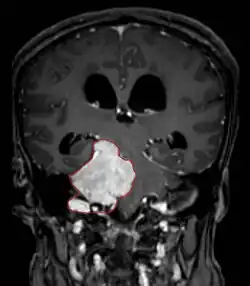

• MRI

• Preferred imaging because it can show dural origin

• Dural tail sign seen in about two-thirds: characteristic marginal thickening that tapers peripherally along the dura

• Isointense on T1, hyperintense (usually homogeneously) on T2, strong enhancement with IV contrast